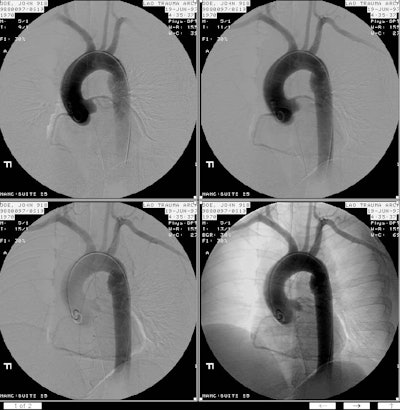

The chest CT and arteriogram on this patient are shown below. The CT demonstrates the presence of standy increased density within the mediastinal fat suggesting a mediastinal hematoma. There is also a focal change in the aortic caliber near the isthmus, and an intralumenal flap can be seen at this level (last image on top row, and first image on bottom row). Despite the CT findings, an arteriogram was performed which again demonstrated the post-traumatic aortic pseudoaneurysm.